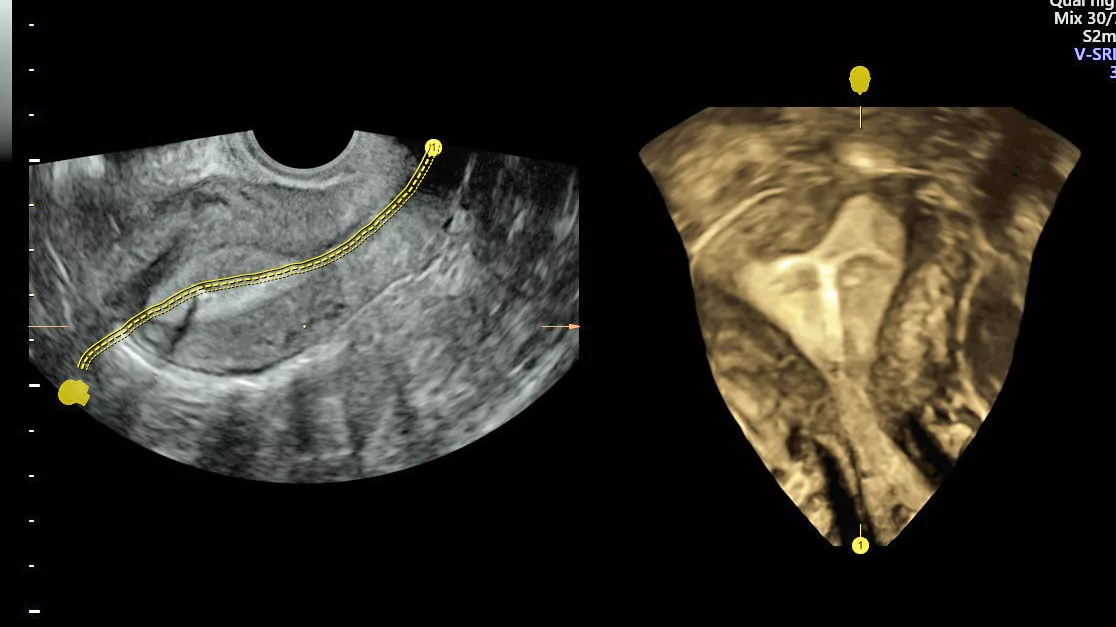

Test de perméabilité tubaire : HyFoSy Hysterosalpingo-Foam-Sonographie

Dans le cadre d’un bilan de la fertilité, la perméabilité des trompes peut être explorée au moyen d’une échographie intravaginale appelée HyFoSy.

Cette échographie permet de visualiser la perméabilité des trompes en injectant une émulsion (ExEm ® Foam Kit), contenant des microbulles d’air, dans la cavité utérine et les trompes.

- L’échographie vaginale est réalisée au fur et à mesure que l’émulsion est injectée. Si l’émulsion blanche passe à travers la/les trompes pour arriver jusqu’à la cavité abdominale, la perméabilité tubaire est démontrée.